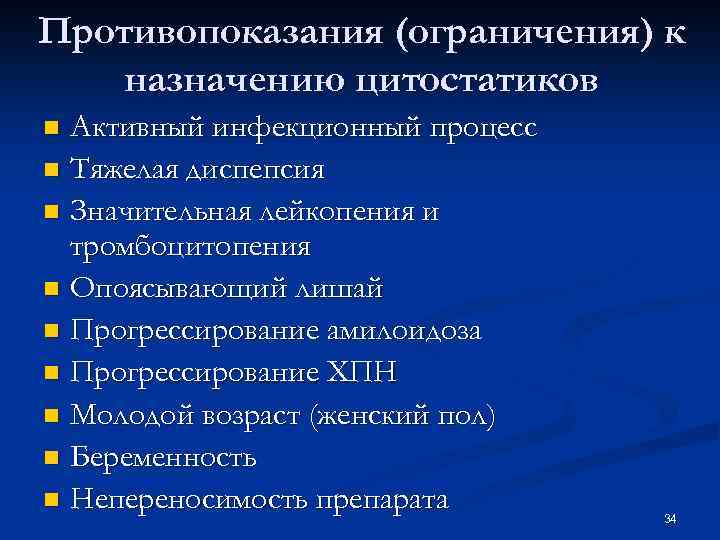

Противопоказания (ограничения) к назначению цитостатиков Активный инфекционный процесс n Тяжелая диспепсия n Значительная лейкопения и тромбоцитопения n Опоясывающий лишай n Прогрессирование амилоидоза n Прогрессирование ХПН n Молодой возраст (женский пол) n Беременность n Непереносимость препарата n 34

Противопоказания (ограничения) к назначению цитостатиков Активный инфекционный процесс n Тяжелая диспепсия n Значительная лейкопения и тромбоцитопения n Опоясывающий лишай n Прогрессирование амилоидоза n Прогрессирование ХПН n Молодой возраст (женский пол) n Беременность n Непереносимость препарата n 34